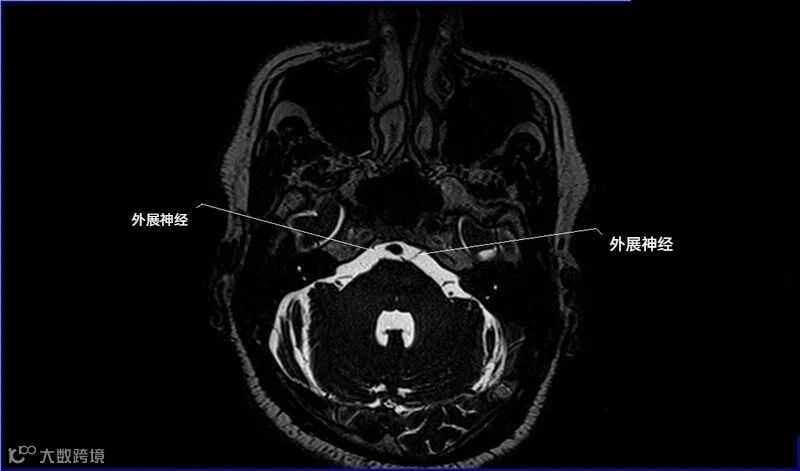

一嗅二视三动眼,四滑五叉六外展,

七面八听九舌咽,迷走及副舌下全。